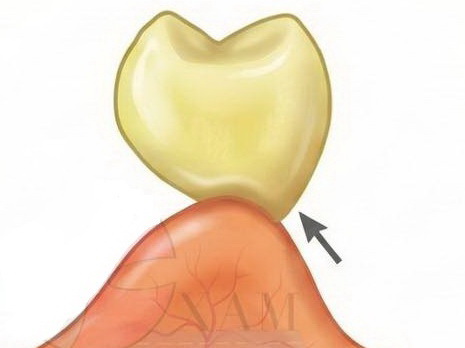

Răng giả nhịp cầu dạng ôm sống hàm (Ridge Lap Pontic)

- Tiếp xúc: Mặt đáy răng giả phủ lên sống hàm ở phía ngoài (má/môi) nhưng được cắt bỏ ở phía trong (lưỡi).

- Đặc điểm: Đảm bảo thẩm mỹ tốt ở mặt ngoài nhìn thấy, đồng thời cố gắng cải thiện khả năng vệ sinh ở phía trong.

- Thực tế trong lâm sàng: Đây là loại nhịp cầu mình ưu tiên dùng cho khoảng 80% các ca lâm sàng, đặc biệt là vùng răng tiền cối và răng trước. Nó đáp ứng được cả hai tiêu chí: vừa giúp bệnh nhân tự tin, vừa giúp họ dễ dàng dùng chỉ nha khoa hoặc bàn chải kẽ răng để vệ sinh mặt đáy nhịp cầu. Một lựa chọn cực kỳ an toàn cho độ bền lâu dài của phục hình.